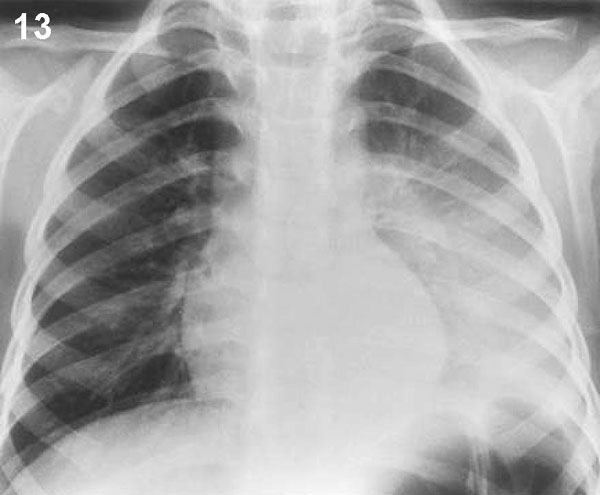

PLACA 13